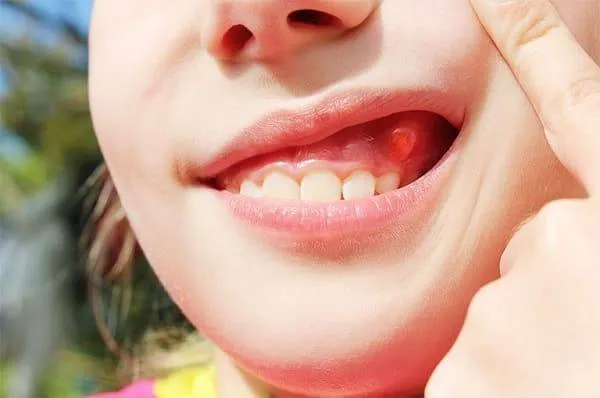

Viêm nướu răng là một trong những vấn đề răng miệng phổ biến nhất ở trẻ em, gây ra không ít lo lắng cho các bậc phụ

Viêm nướu răng là một trong những vấn đề răng miệng phổ biến, đặc biệt ở trẻ em. Khi nói đến hình ảnh viêm nướu răng ở